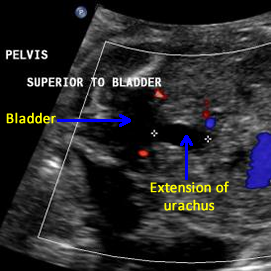

Above. Note the fetal bladder and the anechoic extension of a cyst-like structure superiorly.

Above. Urachal cyst. 23 weeks. Same patient as above showing an anechoic structure extending to the umbilicus. Color Doppler showed no flow within the cyst.